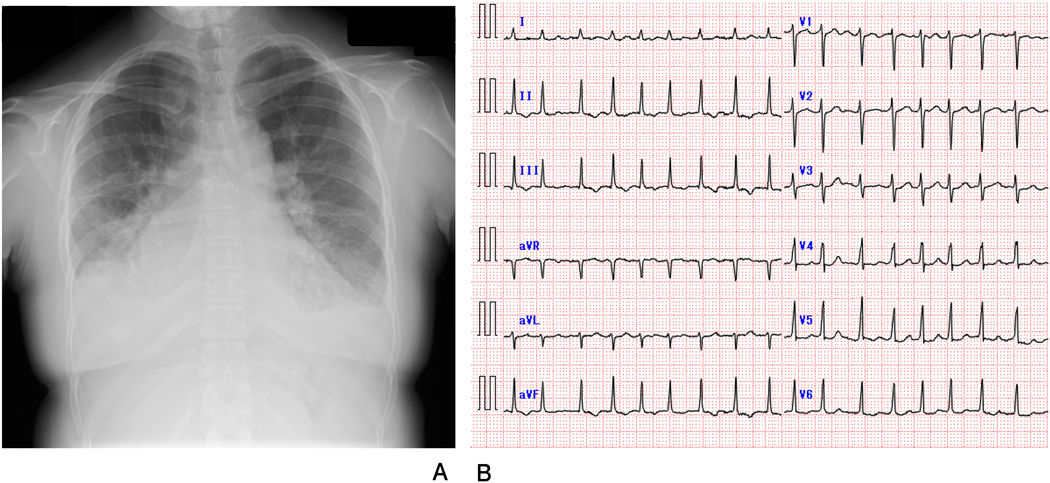

A 30-year-old woman was diagnosed with WS due to a characteristic face and SAS after birth. The Doty procedure was performed at the age of 5 years. Although SAS was relieved, mitral valve prolapse and mitral regurgitation were detected at the age of 10 and progressed to a grade of III at the age of 20. She presented with mental retardation associated with behavioral problems. Removal of teeth plaque was required every 3 months because of malocclusion and dental caries. She was admitted to our hospital because of a remittent fever one month before admission and dyspnea one week before admission after a dental procedure without prior administration of prophylactic antibiotics. On admission, she had a high-grade fever, dyspnea, her eyelids and bilateral lower legs were markedly edematous, and she displayed weight gain of 10 kg in 2 weeks. The resting heart rate was irregular, and auscultation revealed a grade 2/6 regurgitant systolic murmur at the apex. Complete blood counts showed a white blood cell level (WBC) of 1.10×1010/L, a hemoglobin level of 12.5 g/dL, and a platelet level of 143×109/L. The levels of C-reactive protein (CRP) and B-type natriuretic peptide were 0.52 mg/dL (normal range<0.14 mg/dL) and 352.7 pg/mL (normal range<18.4 pg/mL), respectively. Chest radiography showed cardiomegaly, bilateral pulmonary congestion, and bilateral pleural effusion (Fig. 1A). Electrocardiography revealed atrial fibrillation that had never been diagnosed (Fig. 1B) and transthoracic echocardiography revealed left atrium dilatation, mitral valvular anterior leaflet prolapse, and severe mitral regurgitation (Fig. 2A). In transesophageal echocardiography, isoechoic vegetation was identified on the left side of the atrial septum, the impact site of the mitral regurgitant stream (Fig. 2B). Two sets of blood culture were positive for Streptococcus gordonii, which is sensitive to penicillin G and ampicillin. Electrical cardioversion (100 J) restored sinus rhythm, and the patient was subsequently treated with intravenous ampicillin and gentamicin. She became afebrile the next day, and blood cultures were sterile on day 12 of hospitalization. WBC and CRP levels normalized by day 27, and the vegetation disappeared completely on day 43. Antibiotic administration was discontinued on day 44. The degree of mitral regurgitation remained severe despite the improvement in symptoms and laboratory data. Consequently, we performed mitral annuloplasty, pulmonary vein isolation, and left appendage closure 3 months after admission. The anterior mitral leaflet was large and thick, and the posterior leaflet was smaller in dimension (Fig. 3A). An incision was made on a part of the anterior mitral leaflet, and plication of the bilateral commissure was performed. The resected specimen of the mitral valve showed minimal chronic inflammation with myxoid degeneration (Fig. 3B). She was discharged on day 14 after surgery without any complications.

Fig. 1 (A) Chest radiography shows cardiomegaly, bilateral pulmonary congestion, and bilateral pleural effusion. (B) Electrocardiogram shows atrial fibrillation with an irregular R–R interval.